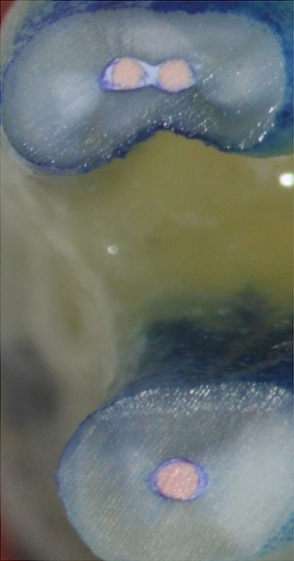

Figure 1. THROUGH Figure 3. Root filled with bioceramic sealer cut at different distances from the apex (left to right: 0.5, 1.5, and 3.0 mm). One gutta-percha point is used as a plugger to move the sealer using hydraulic pressure. Note the irregularities are very well filled.

Figure 1

Figure 2